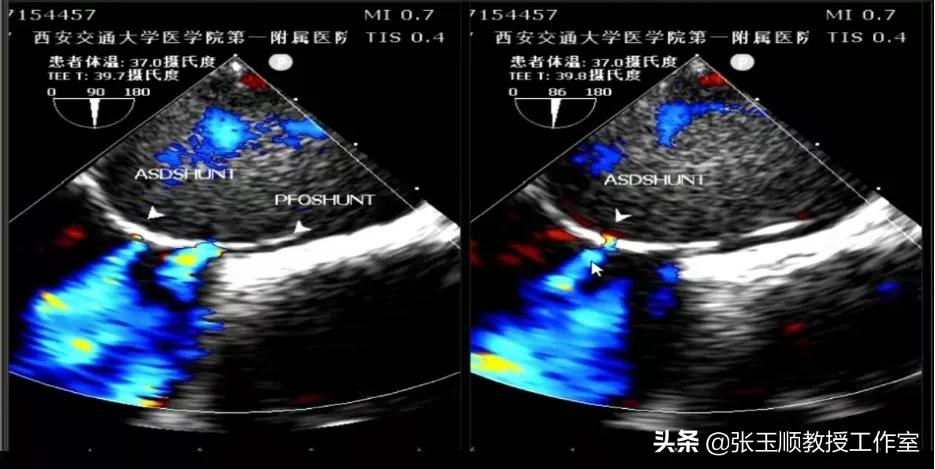

为了进一步确诊,医院又给李先生做了食道超声心动图,发现李先生房间隔飘软,形成房间隔瘤,不但有卵圆孔未闭,还有小房间隔缺损。做食道超声发泡,除外了其他来源,证实微气泡来源于心脏。但是否与剧烈咳嗽后有关,尚需进一步评估(图2、3)。

图2 食道超声:房间隔缺损,卵圆孔未闭

图3 房间隔瘤和巨大卵圆孔未闭